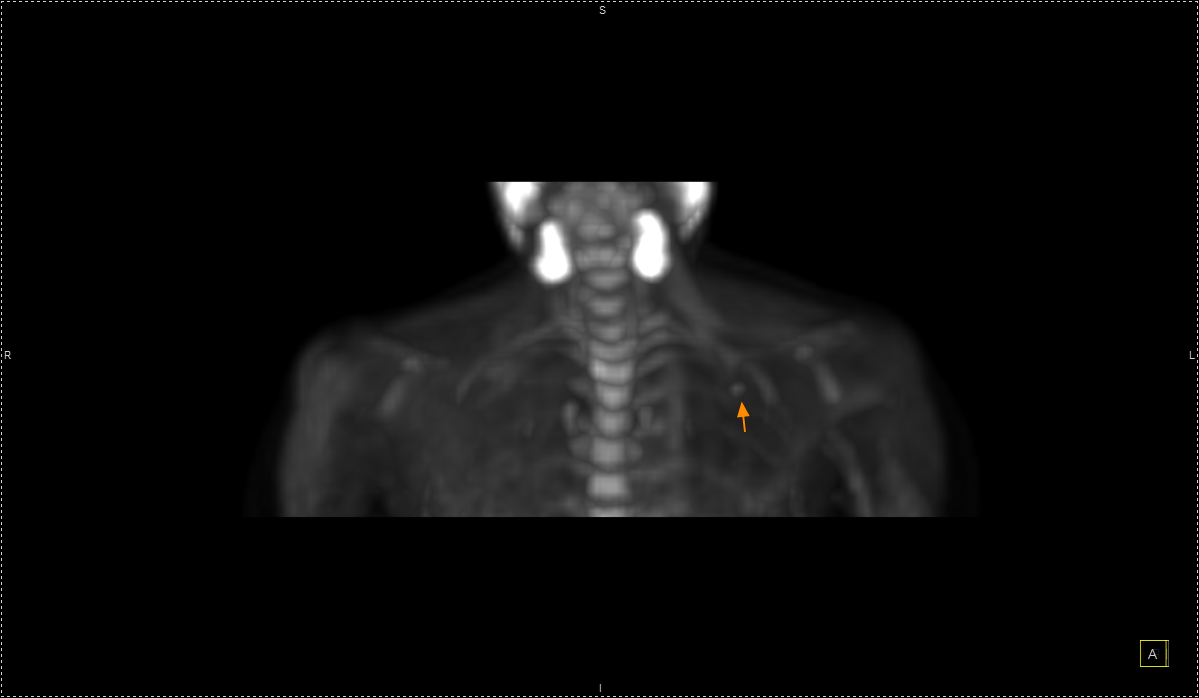

Η εξέταση είναι ανώδυνη και ασφαλής, πραγματοποιείται μετά από ενδοφλέβια χορήγηση ραδιοφαρμάκου (συνήθως ¹⁸F-FDG) και καλύπτει συνήθως ολόκληρο το σώμα – από την κορυφή της κεφαλής έως τα πέλματα.

Στο Κέντρο PET/CT πραγματοποιούνται εξειδικευμένες εξετάσεις που καλύπτουν ένα ευρύ φάσμα κλινικών εφαρμογών στη σύγχρονη Πυρηνική Ιατρική. Ανάλογα με το είδος του προβλήματος και τη φύση της νόσου, χρησιμοποιούνται διαφορετικά ραδιοφάρμακα για τη μελέτη συγκεκριμένων βιολογικών μηχανισμών.